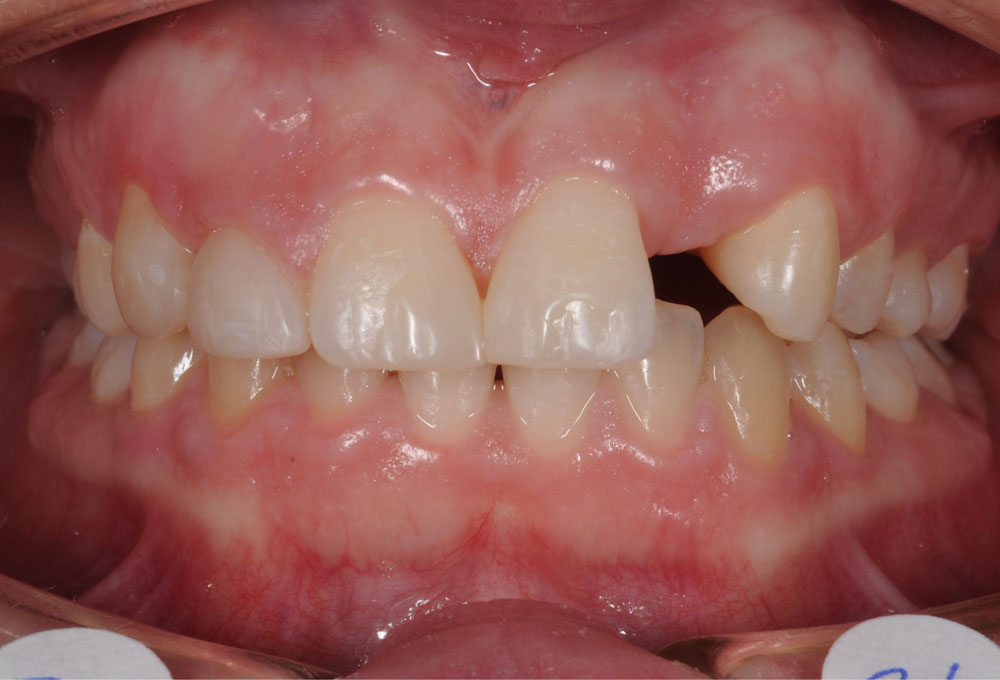

In questa terapia ortodontica si procede con il recupero dello spazio che sarebbe stato a disposizione dell’elemento del dente agenesico, al fine di una successiva sostituzione protesica dei denti mancanti.

Genericamente si ricorre a questa opzione nei casi in cui l’ingranaggio occlusale, la funzione masticatoria e l’estetica del sorriso siano già buoni.

La riapertura degli spazi viene eseguita per perfezionare le posizioni dentali e favorire la successiva riabilitazione protesica.

In questo caso, l’Ortodontista richiede la preventiva valutazione riabilitativa protesica al collega dentista, che fornirà le informazioni necessarie in merito alle future esigenze di spazio e posizione dentale per una miglior esecuzione del lavoro protesico previsto.